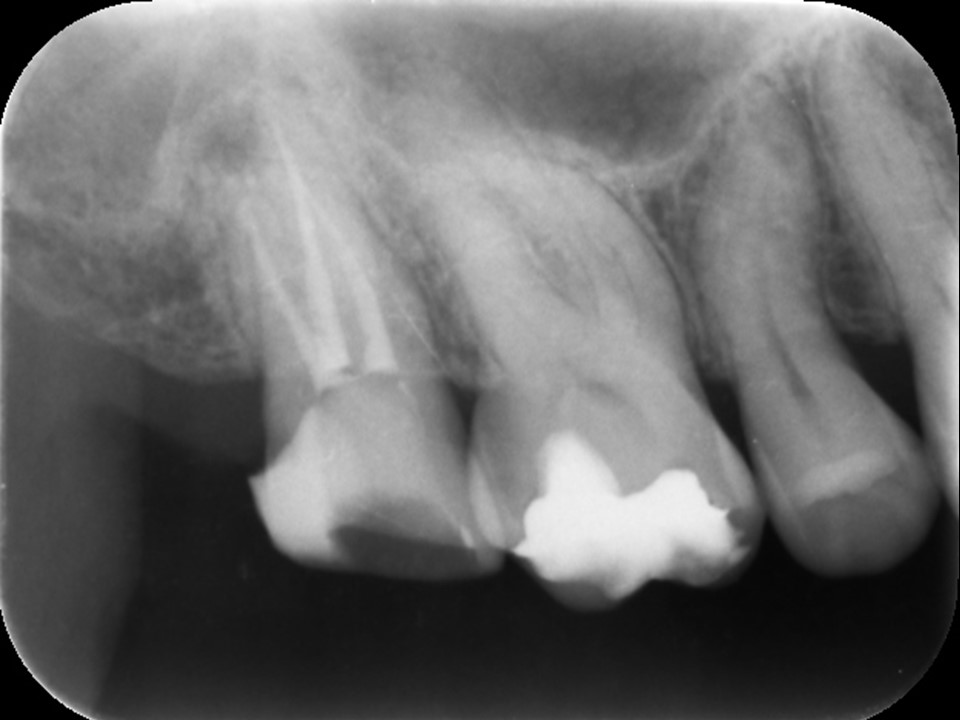

初診時CT。根管治療を何度も繰り返し行ったことで、歯根は無駄に削られて歯質が薄くなり、歯根の先端には穿孔(パーフォレーション)を生じていた。根尖病巣は認めない。

同CT画像。ファイバーコアで土台を補強し、仮歯の状態で3か月の経過観察を行った。初診時にあった歯の違和感は完全に消失したため、オールセラミックで補綴処置を行うこととした。